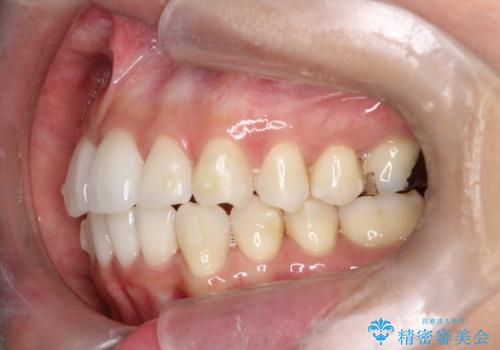

【インビザライン】前歯の凸凹をIPRで改善

- 前歯の凸凹を主訴に来院されました。

前歯を並べるために歯と歯の間にヤスリを入れてわずかに歯を削ることでスペースを確保しています。

歯と歯の間にヤスリを入れてわずかに歯を削ることでスペースを確保する処置をIPRと呼びます。

当院では拡大鏡を用いて丁寧に処置することで歯冠形態を損なわずに行うことができます。